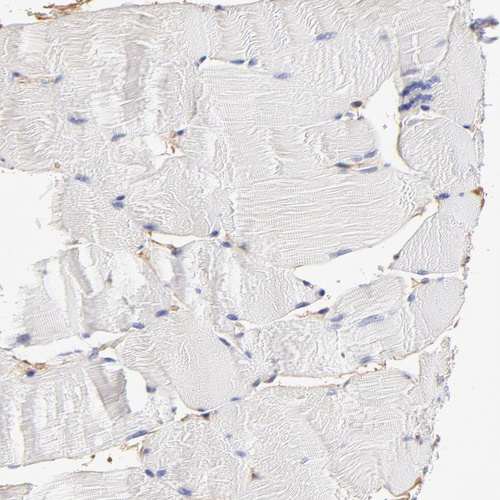

Immunohistochemistry analysis in human small intestine and skeletal muscle tissues using HPA003326 antibody. Corresponding CD2AP RNA-seq data are presented for the same tissues.